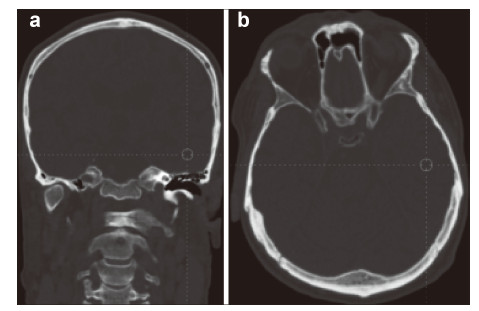

The obtained multi‐level data about the condition of the patient’s brain must be provided at contemporary carriers (CD,DVDs,flash drives,etc.) for the bioinformation analysis and they must be recorded in DICOM standard. The requirements for the research at this stage are the following: (1) No less than 1.5 Tesla MRI. (2) MRI tractography of conduction pathways in the site of injury of the brain/spinal cord. (3) MRI angiography of the brain vessels. (4) PET of the brain or a whole body,for spinal cords the standard radioisotopes of glucose PET must be done. (5) No less than 32 slice spiral CT of the brain or the spinal cord and spine. (6) Cerebral EEG mapping must be on the EEG equipment with the software for 3D local modeling of the bioelectrical activity of the brain/spinal cord. (7) MEG of the brain with 3D modeling.

The time period between different imaging tests should be not more than a week. All imaging tests that were done at the preparatory stage for the examination can be used at the next stage to monitor the effectiveness of the therapy. The imaging data can be fused into 3D maps of the brain with the help of the Multimodal fusion 3D software of the Cyberknife robotic radiosurgery system or similar systems for stereotaxic radiotherapy of other manufacturers. With this approach a three‐dimensional multi‐level mapped model of the information structure of the damaged NT of the brain/spinal cord of the nerve or mental disease case can be represented as the set of the tables of local data,that correlate them with anatomical formations in the brain so that the personalized functional 3D map of pathological changes and damages the NT of the specific case. Such a 3D map can be the basis for the marking and stereotaxic targeted therapeutic radio‐bioengineering effect of IR on the brain or spinal cord. This stage of the proposed treatment of nervous and mental diseases can be illustrated by the clinical case of the patient B. Figures 2-7 represent the data of different stages of the technology of multilevel fusion of the data of computerized tests.

|